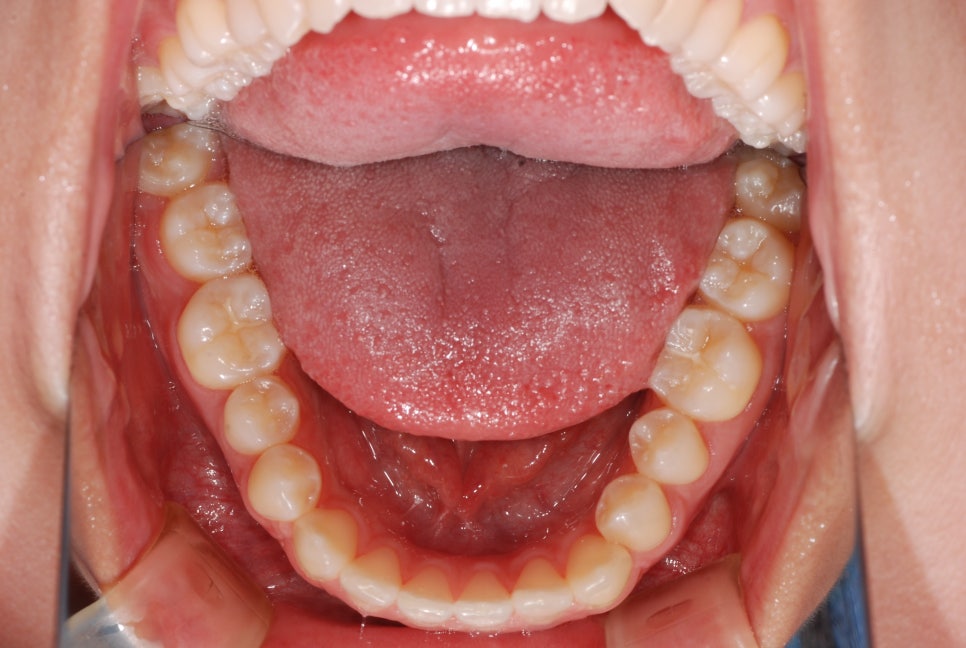

아랫턱 전체 치열을 후방으로

이동하기 위해서는 발치가 필요합니다.

그래야 뒤로 움직일 수 있는

공간이 충분히 확보됩니다.

장치(브라켓)를 달고

변위된 치아를 제 자리로 이동시킴과 동시에

아랫치열을 후방으로 밀기 시작합니다.

그래야 안정적인 교합을

유도할 수 있기 때문이죠.

아랫 치열을 당기는 힘을

조절하기 위해서 스프링을 사용합니다.

✔동시에 어금니는 정출 즉,

위로 올라오도록 유도하고

아래턱은 시계방향으로 회전하여

전치부의 정상적인 맞물림을 위해

윗쪽 앞니의 정출을 유도합니다.

더불어 미니 임플란트를 활용하여

아래 치열의 후방 이동을

더욱 확실하게 유도합니다.